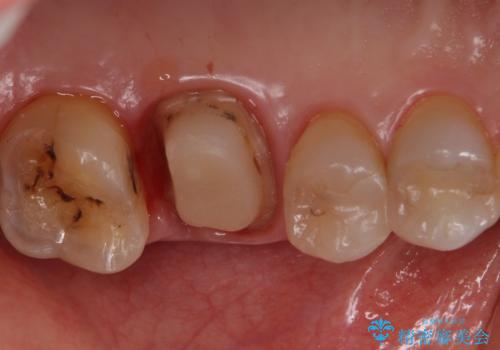

- 検査の結果被せ物の下に虫歯が確認された患者様です。

虫歯を取りきった後セラミッククラウンでの修復処置を行います。

被せ物の裏側の虫歯は被せ物を取らないと除去できません。

今回は過去に治療された部分をすべてやり直しました。